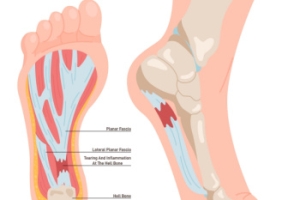

Plantar fasciitis is the inflammation of the plantar fascia, a thick band of tissue that connects the heel bone to the toes and supports the arch of the foot. This condition is a common source of heel pain, especially during the first steps in the morning or after long periods of rest. Symptoms may include sharp or aching pain in the heel or arch of the foot, often worsening with activity. Risk factors for developing plantar fasciitis include prolonged standing, high-impact activities, obesity, and wearing unsupportive footwear. Individuals with flat feet or high arches may also be more prone to this condition. If you have heel pain, it is suggested that you contact a podiatrist sooner rather than later who can accurately diagnose and treat plantar fasciitis.

Plantar fasciitis is one of the most common causes of heel pain. The plantar fascia is a ligament that connects your heel to the front of your foot. When this ligament becomes inflamed, plantar fasciitis is the result. If you have plantar fasciitis you will have a stabbing pain that usually occurs with your first steps in the morning. As the day progresses and you walk around more, this pain will start to disappear, but it will return after long periods of standing or sitting.

There are some risk factors that may make you more likely to develop plantar fasciitis compared to others. The condition most commonly affects adults between the ages of 40 and 60. It also tends to affect people who are obese because the extra pounds result in extra stress being placed on the plantar fascia.

Plantar fasciitis is one of the most common causes of heel pain. The plantar fascia is the thick band of tissue that connects the heel bone to the toes. When this band of connective tissue becomes inflamed, plantar fasciitis occurs. Fortunately, this condition is treatable.

There are several factors that may put you at a greater risk for developing plantar fasciitis. One of the biggest factors is age; plantar fasciitis is common in those between the ages of 40 to 60. People who have jobs that require them to be on their feet are also likely to develop plantar fasciitis. This includes factory workers, teachers, and others who spend a large portion of their day walking around on hard surfaces. Another risk factor is obesity because excess weight can result in extra stress being placed on the plantar fascia.

People with plantar fasciitis often experience a stabbing pain in the heel area. This pain is usually at its worst in the morning, but can also be triggered by periods of standing or sitting. Plantar fasciitis may make it hard to run and walk. It may also make the foot feel stiff and sensitive, which consequently makes walking barefoot difficult.

If you suspect that you have plantar fasciitis, meet with your podiatrist immediately. If left untreated, symptoms may lead to tearing and overstretching of the plantar fascia. The solution is early detection and treatment. Be sure to speak with your podiatrist if you are experiencing heel pain.